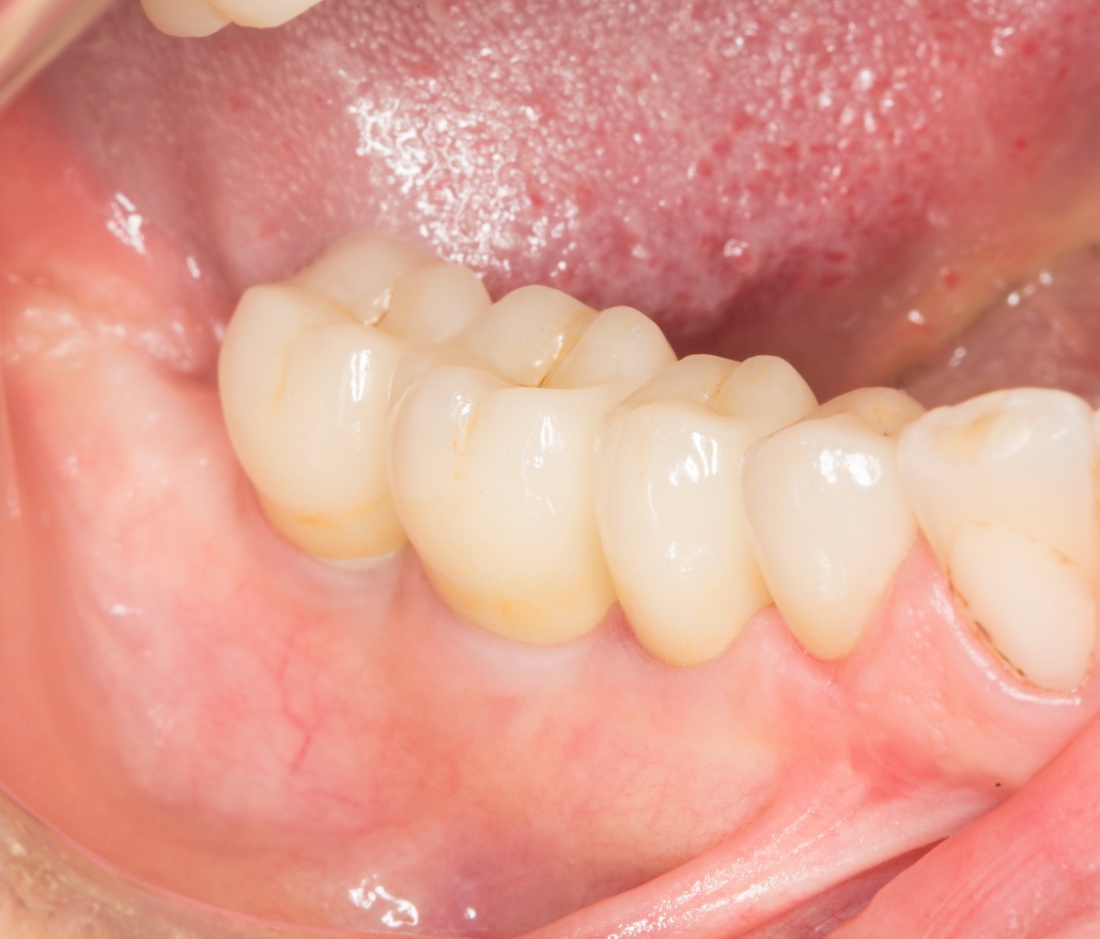

Остеопластика или «наращивание костной ткани» при имплантации — выбор метода и отдаленные результаты.